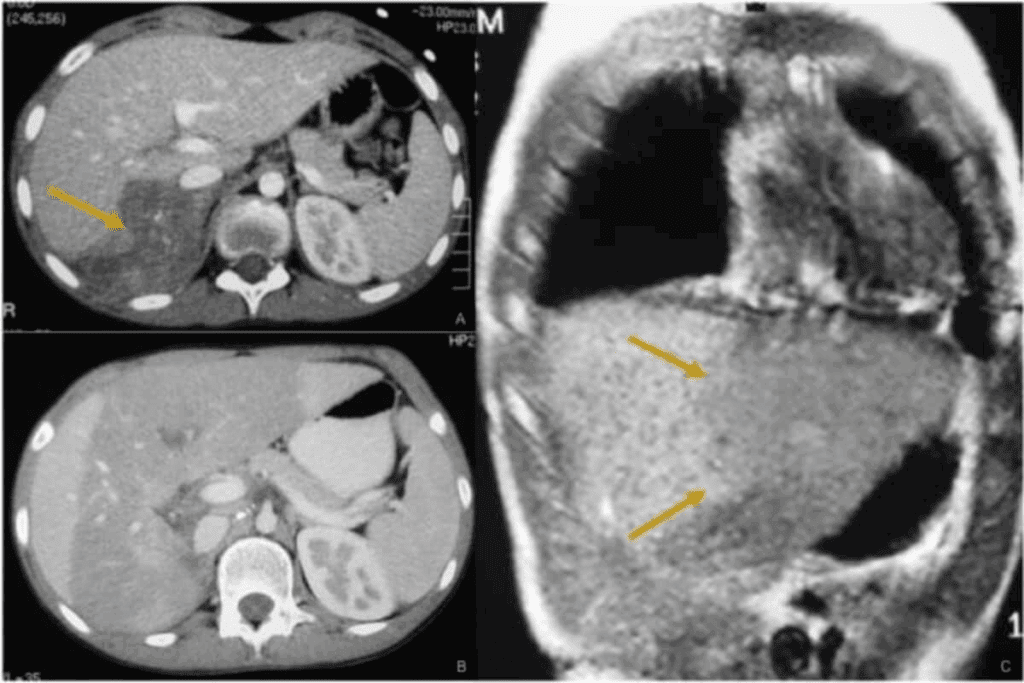

Imaging Techniques

Imaging is vital for finding neuroblastoma. We use different imaging tools to see the tumor and how big it is.

- Ultrasound: Often used first, mainly for belly masses.

- Computed Tomography (CT) Scan: Gives detailed images to see the tumor’s size and where it is.

- Magnetic Resonance Imaging (MRI): Shows detailed images, great for soft tissue and brain effects.